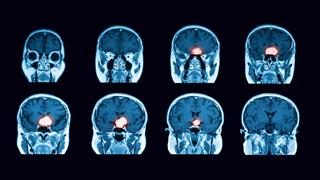

Όγκοι της υπόφυσης: Πού πρέπει να στοχεύει η χειρουργική θεραπεία

Nέα μελέτη δημοσίευσαν πρόσφατα ερευνητές των Πανεπιστημίων Κέιμπριτζ και Λονδίνου, η οποία παρουσιάζει την κλινική έκβαση της χειρουργικής θεραπείας αδενωμάτων της υπόφυσης.